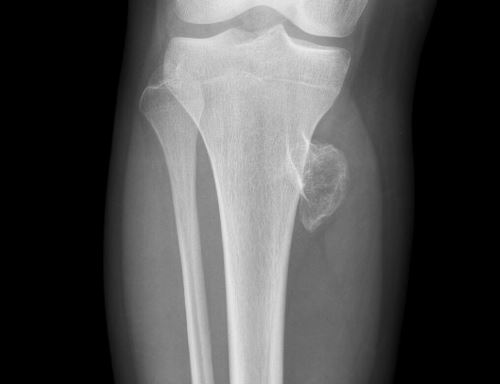

Обнаружить экзостоз можно на рентгеновском снимке, или при пальпации, которую приводит врач на осмотре.

По форме образование может иметь быть грибовидным, шиповидным, как цветная капуста.

В коленном суставе экзостома растет рядом с концом бедренной трубчатой кости или внутри сустава.